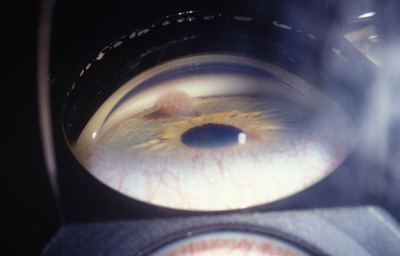

Melanoma sólido nodular del Iris

Archivo Fotográfico Dr. Francisco Barraquer.

Melanoma sólido nodular del Iris

Archivo Fotográfico Dr. Francisco Barraquer.

Melanoma sólido nodular del Iris

Archivo Fotográfico Dr. Francisco Barraquer.

Vista frontal del Melanoma sólido

Archivo Fotográfico Dr. Francisco Barraquer.

Melanoma sólido nodular del Iris con lente de Gonioscopía

Archivo Fotográfico Dr. Francisco Barraquer.

El circunscrito, es una masa solitaria nodular en el estroma del Iris, con variables grados de pigmentación, con vasos nutricios intrínsecos en el estroma o dentro del ángulo. (31,32,33)